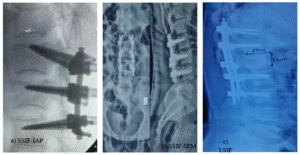

Figure 01. a) SSIF-IAP (short segment internal fixation with inclined angle poly axial) screw. b) SSIF-SFM (short segment internal fixation with straight forward monoaxial) screw. c) LSIF (long segment internal fixation) screw.